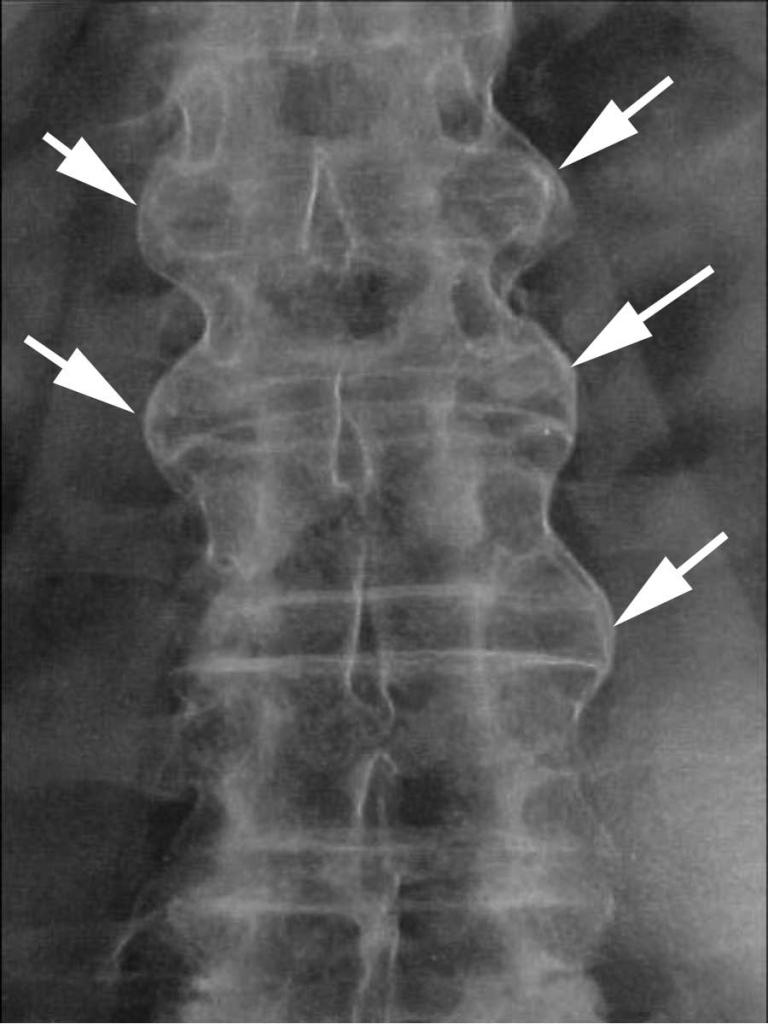

Наиболее часто межпозвонковая протрузия в области пояснично-крестцового отдела позвоночника выявляется во время осмотра у врача. Тем не менее, рекомендуется провести рентгенографию с контрастным веществом и компьютерную томографию для более точной диагностики. В случае запущенной стадии заболевания, обследование может показать уменьшение диаметра спинного мозга и наличие воспалительных процессов, возникающих при повреждении любого межпозвоночного диска.